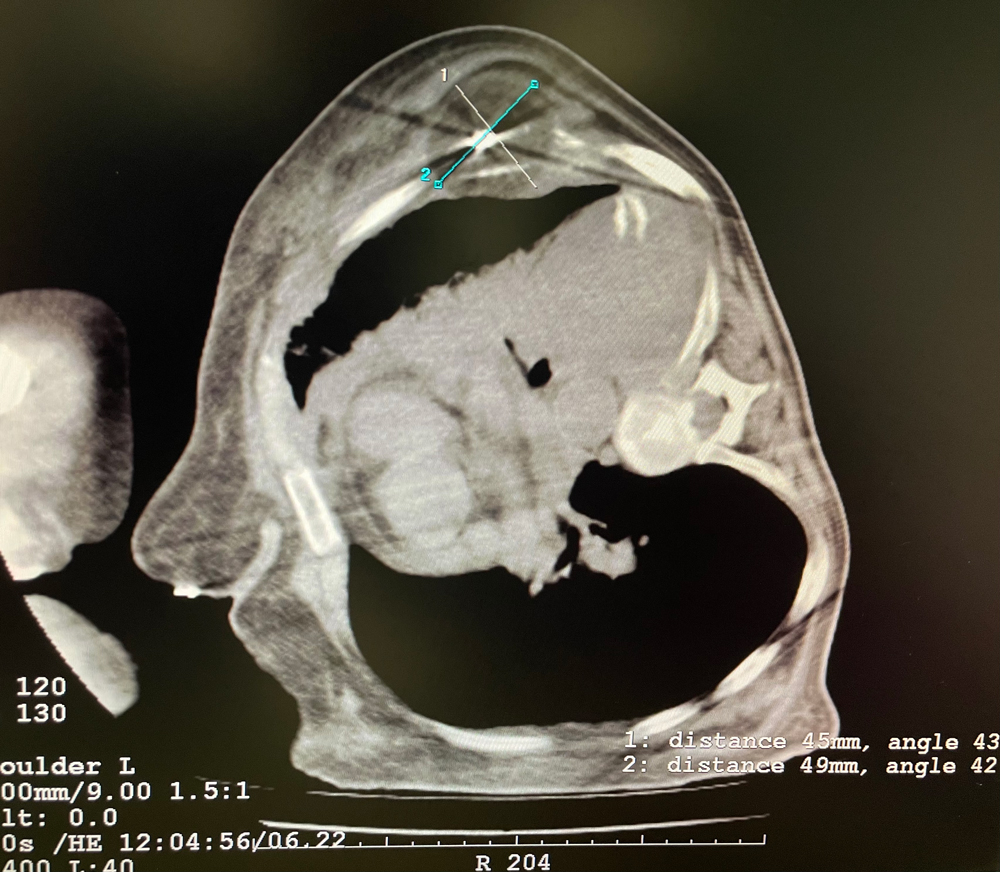

女,42岁,复发性脂肪瘤,病灶位于右侧膝关节,直径大小13cm。采用双针方案,共进行6个冻融循环,最大冰球直径达8.2cm,术中多方位治疗全面覆盖病灶范围。患者术后状况良好。